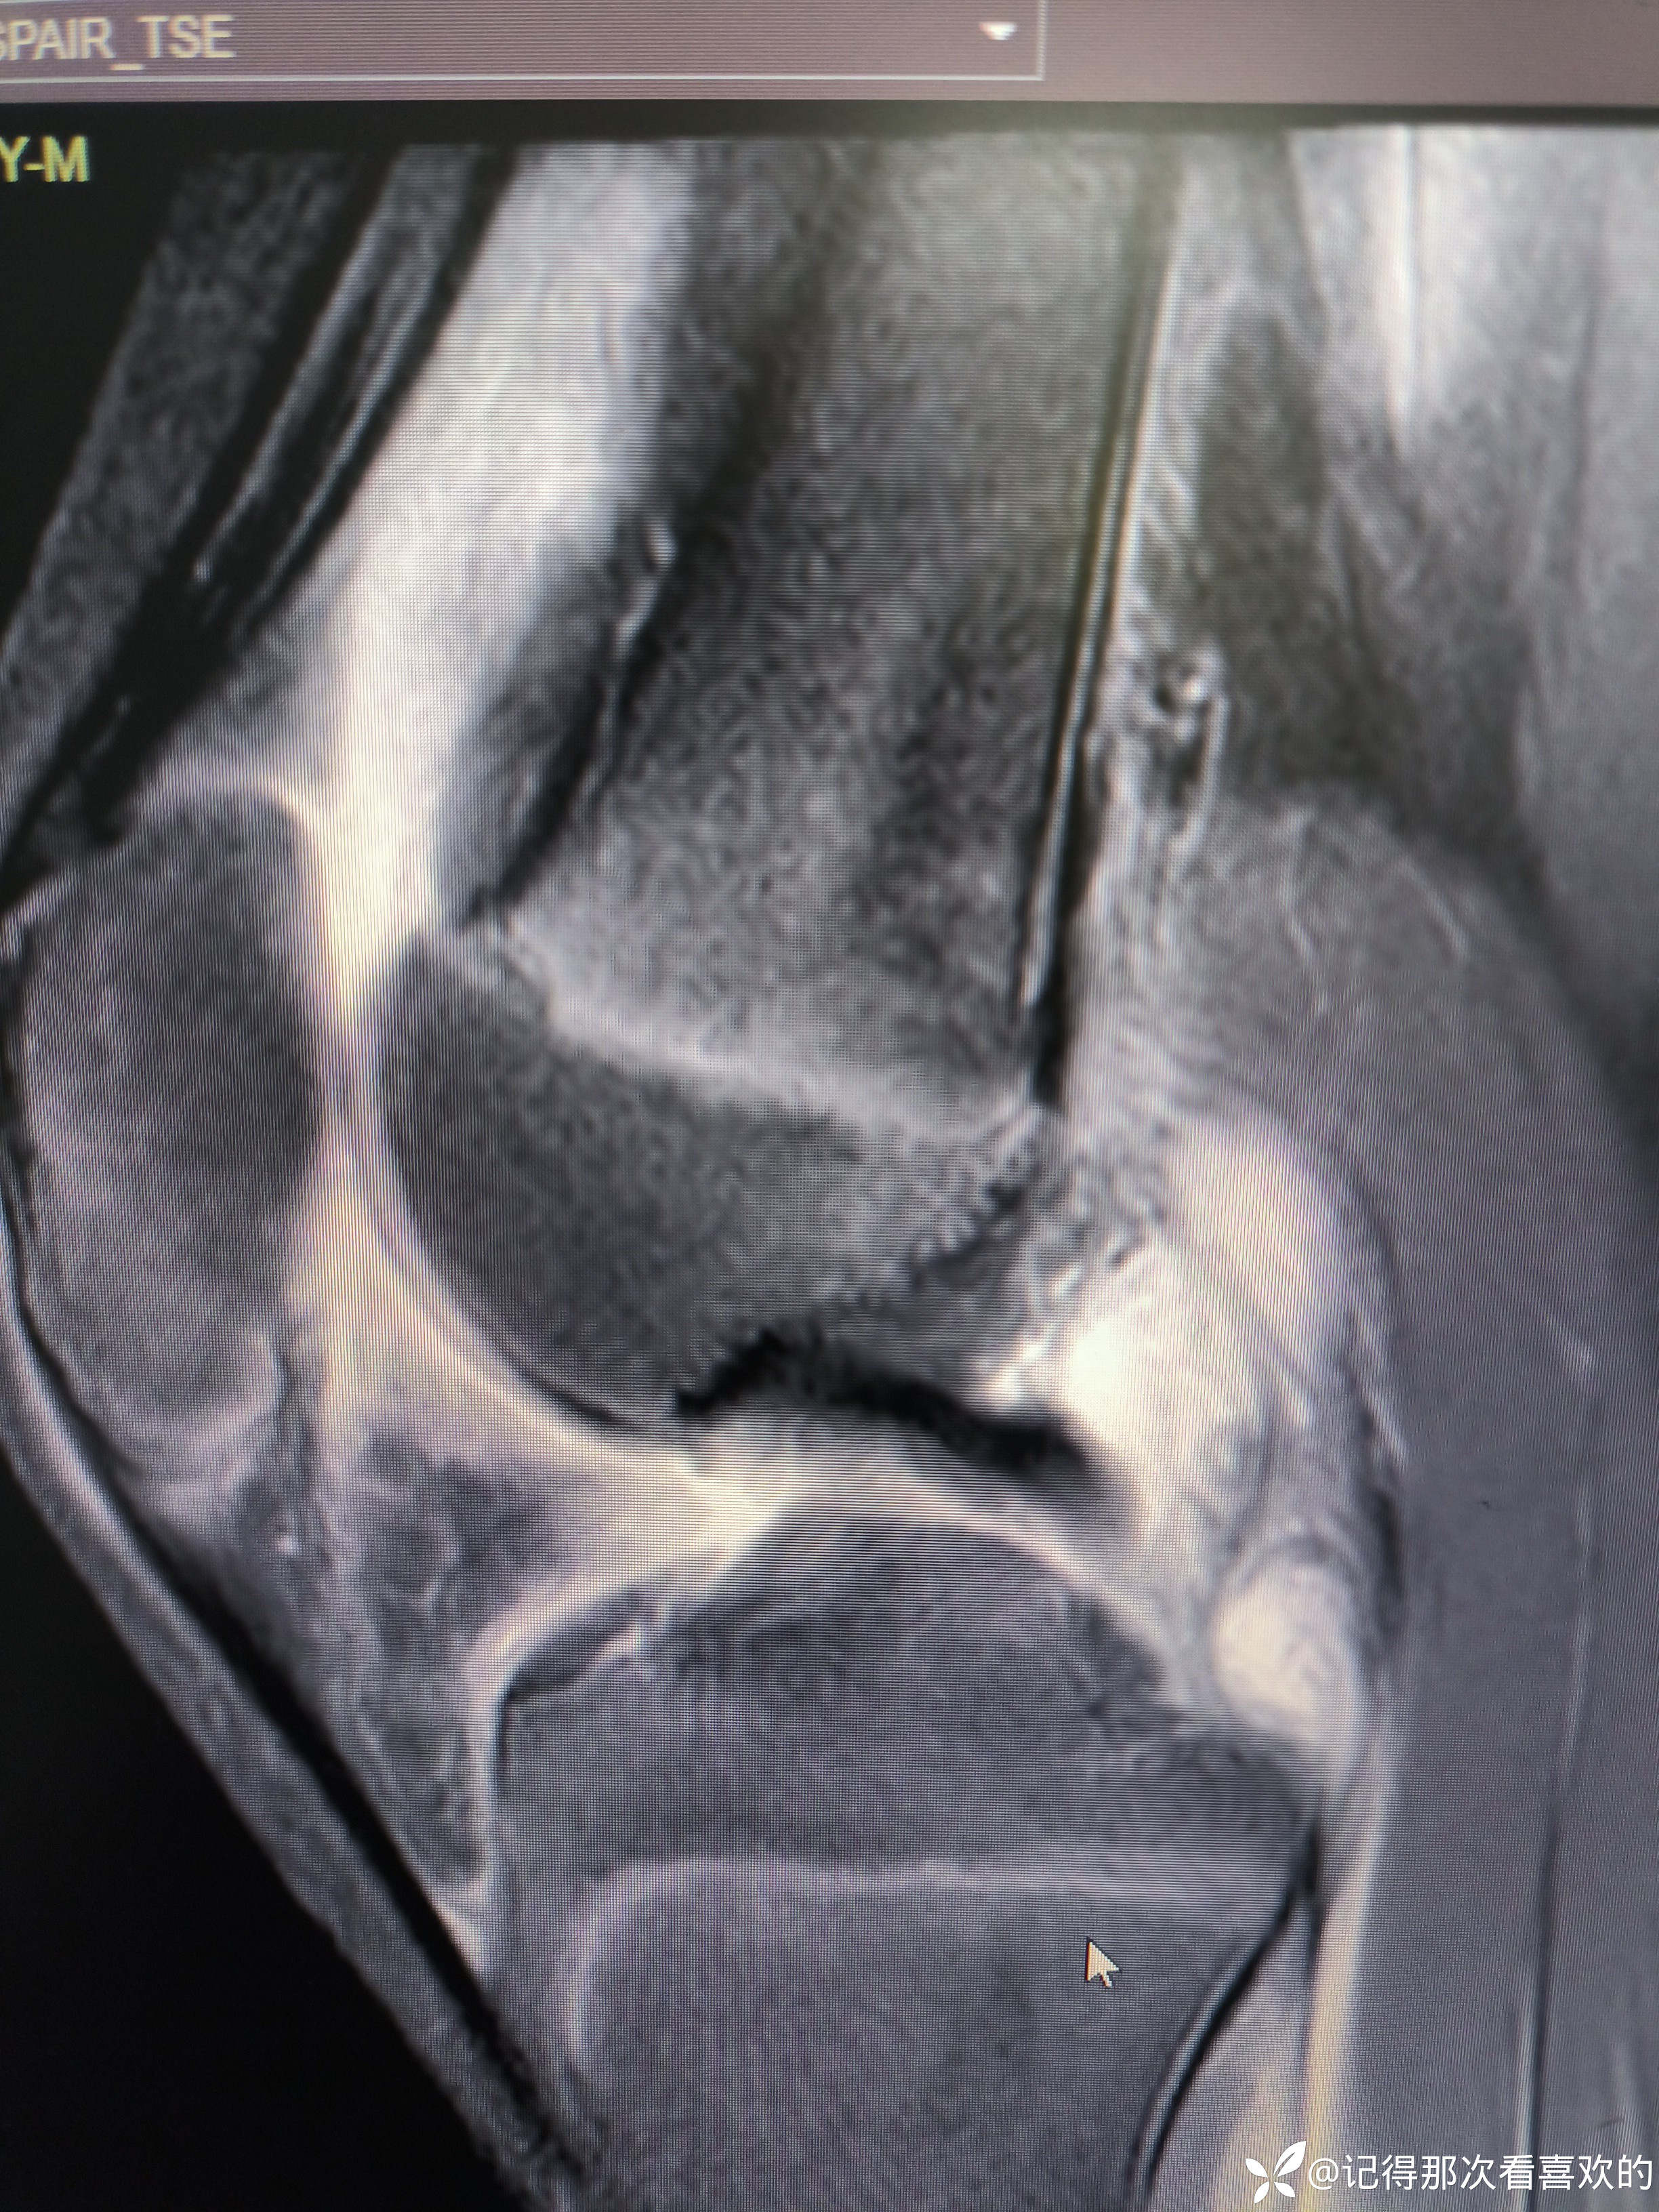

病例特点:患者钟某 男,14岁,以"髋、膝、足肿痛1年余,加重3日。"为主诉入院。现病史:缘于1年前无明显诱因出现左侧髋关节、双足跟、左踝关节、右足第一足趾关节肿胀、疼痛, 疼痛呈持续性,多于阴雨天、活动后症状加重,疼痛未向他处放射、转移,症状严重时行走困难。遂就诊于我科,查"HLA-B27(+)、CRP 70mg/L、骶髂MR:骶髂关节肿胀",诊断为"强直性脊柱炎",先后予皮下注射"司库其尤单抗150mg qw、阿达木单抗40mg q2w",上述症状较前好转,此后不规律用药,于半年前自行停用上述药物,未再规律随诊。3日前再发左膝、双肘关节肿痛,性质同前,程度较前加重,影响行走,伴有发热,体温最高达39℃,自行服用退烧药(具体不详)后体温较前下降,上述关节肿痛无明显改善。现为求进一步治疗,就诊我院,门诊拟"强直性脊柱炎"收住入院。体格检查:T36.6℃ P138次/分 R50次/分BP/120/68mmHg 专科情况:生命征平稳,神志清楚,双肺呼吸音清,未闻及干湿啰音,心律齐,各瓣膜听诊区未闻及杂音,全腹软,无压痛及反跳痛,未触及包块,双肘、左膝关节肿胀、压痛、触之皮温高。双下肢无浮肿,病理征未引出。

诊断依据:1.患者青年男性,以"髋、膝、足肿痛1年余,加重3日。"为主诉入院,疼痛多于阴雨天、活动后加重,病情严重时行走困难。2.查体:双时、左膝关节肿胀、压痛、触之皮温高。3.既往辅助检查提示HLA-B27阳性、影像学提示骶且关节炎。4.根据患者症状、体征及既往诊疗病史,目前考虑诊断强直性脊柱炎。5.余诊断根据既往病史可明确。

诊疗计划:1.入院予二级护理,监测血压、脉搏、呼吸。2.入院完善三大常规、凝血、生化、骶髂MR、彩超、CT、心电图等相关检查评估病情。3.治疗上暂予抗炎镇痛,辅以护胃治疗,待相关检查结果回报后进一步治疗,本次就诊拟行生物制剂治疗,予完善骨保护药物,传染病相关检查排除禁忌症,患者本次发病伴有发热达39℃,追问病史患者诉偶有干咳不适,目前已改善,予完善呼吸道病原学检查明确病情。4.患者Padua评分1分,属于发生VTE低危风险,实行VTE基本预防,动态评估Padua评分。5.已将目前病情及现有临床诊断以及存在疾病复杂性、个体的差异性、对治疗的反应不同、鉴于目前医学技术水平有限,和下一步相关诊疗详细充分告知患者家属,取得家属的理解并同意配合下一步诊疗及检查。6.NRS-2002评分3分,目前患者营养状态尚可,进食情况尚可,根据病情变化动态评估。